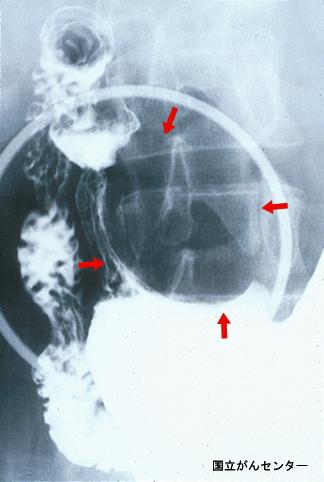

疾病(病理主体)的分类良性非上皮性肿瘤/脂肪瘤

部位(按器官分)胃(部位)/前庭

检查方法X线

肿瘤最大直径40以上